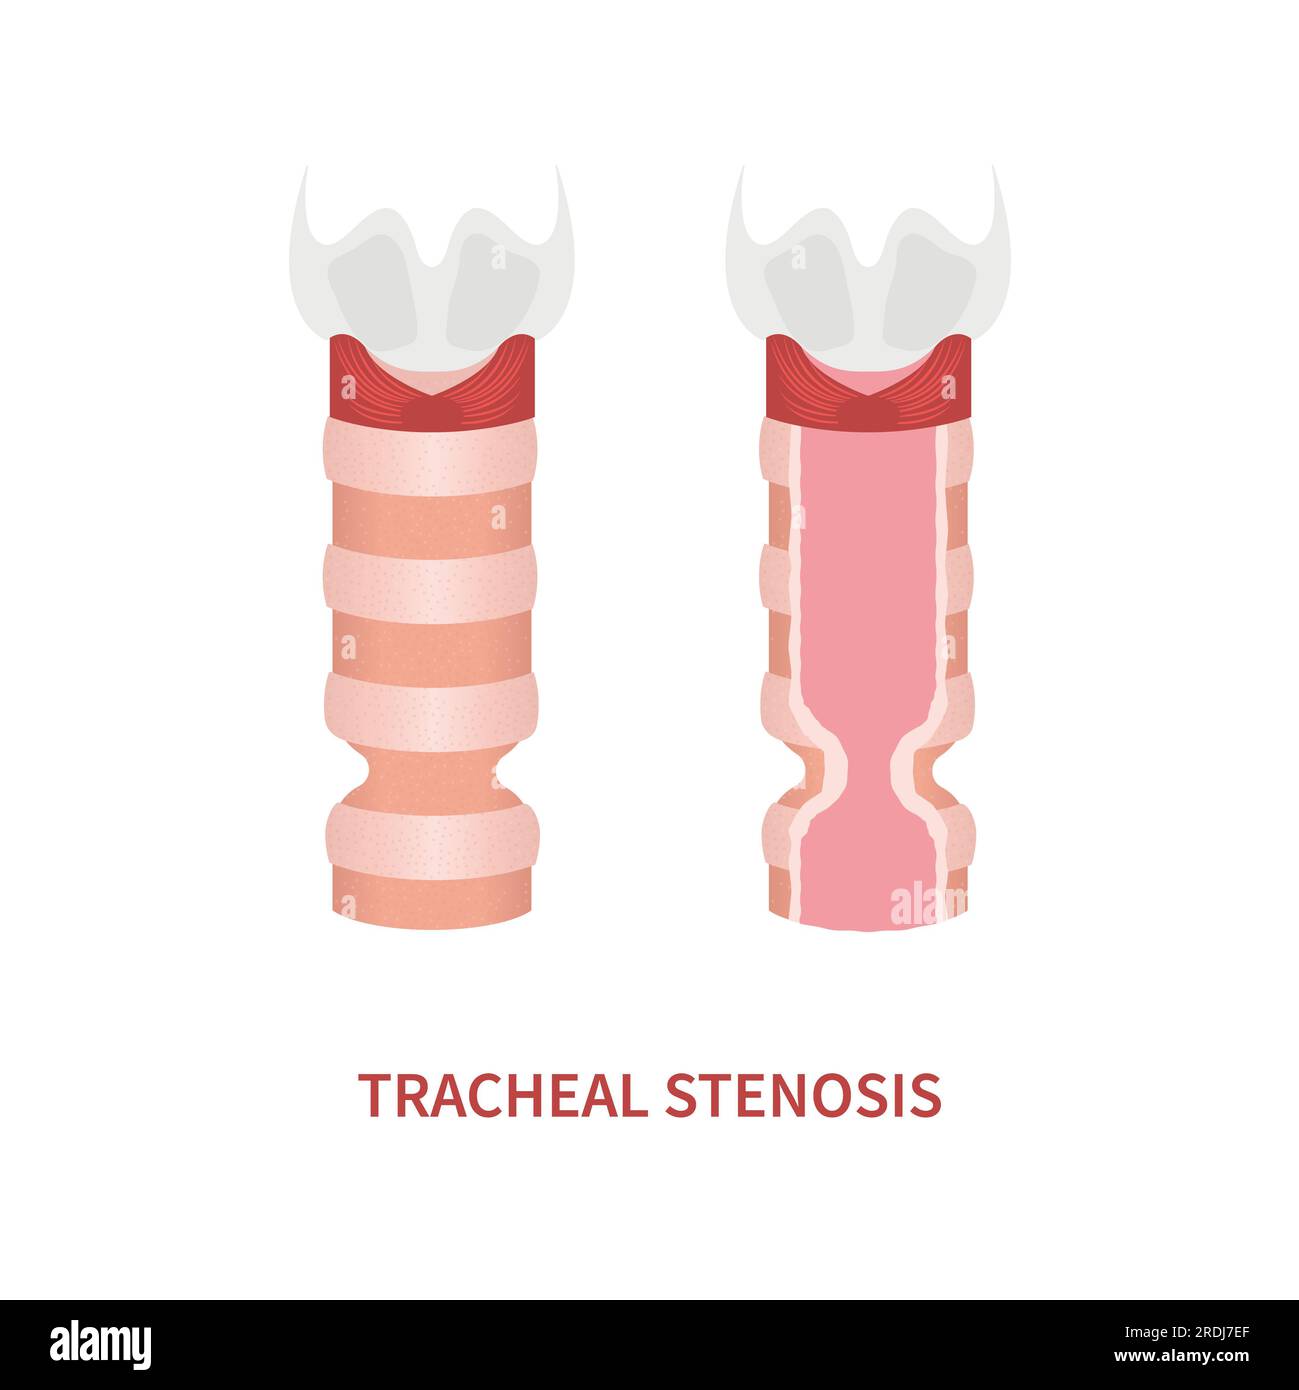

Tracheal stenosis, illustration Stock Photohttps://www.alamy.com/image-license-details/?v=1https://www.alamy.com/tracheal-stenosis-illustration-image559123361.html

Tracheal stenosis, illustration Stock Photohttps://www.alamy.com/image-license-details/?v=1https://www.alamy.com/tracheal-stenosis-illustration-image559123361.htmlRF2RDJ7FD–Tracheal stenosis, illustration

Tracheal stenosis, illustration Stock Photohttps://www.alamy.com/image-license-details/?v=1https://www.alamy.com/tracheal-stenosis-illustration-image559123373.html

Tracheal stenosis, illustration Stock Photohttps://www.alamy.com/image-license-details/?v=1https://www.alamy.com/tracheal-stenosis-illustration-image559123373.htmlRF2RDJ7FW–Tracheal stenosis, illustration

Tracheal stenosis, illustration Stock Photohttps://www.alamy.com/image-license-details/?v=1https://www.alamy.com/tracheal-stenosis-illustration-image559123334.html

Tracheal stenosis, illustration Stock Photohttps://www.alamy.com/image-license-details/?v=1https://www.alamy.com/tracheal-stenosis-illustration-image559123334.htmlRF2RDJ7EE–Tracheal stenosis, illustration

Tracheal stenosis, illustration Stock Photohttps://www.alamy.com/image-license-details/?v=1https://www.alamy.com/tracheal-stenosis-illustration-image559123343.html

Tracheal stenosis, illustration Stock Photohttps://www.alamy.com/image-license-details/?v=1https://www.alamy.com/tracheal-stenosis-illustration-image559123343.htmlRF2RDJ7ER–Tracheal stenosis, illustration

Tracheal stenosis, illustration Stock Photohttps://www.alamy.com/image-license-details/?v=1https://www.alamy.com/tracheal-stenosis-illustration-image559123335.html

Tracheal stenosis, illustration Stock Photohttps://www.alamy.com/image-license-details/?v=1https://www.alamy.com/tracheal-stenosis-illustration-image559123335.htmlRF2RDJ7EF–Tracheal stenosis, illustration